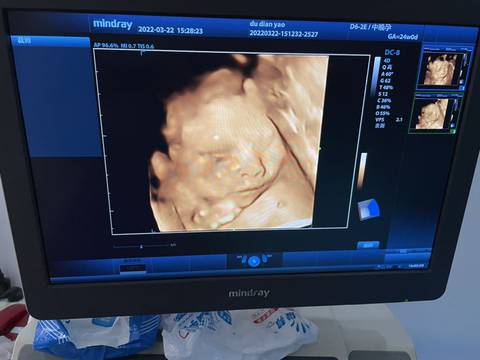

能看出是男生女生吗哈哈哈好好奇啊

你好,我们是看不出来的,只要是健康的宝宝,都是上帝赐予的礼物,孕期定期检查,祝心想事成 。

亲,这个上面来看确实判断不了的,顺其自然就好了,别给自己太大压力,心想事成。